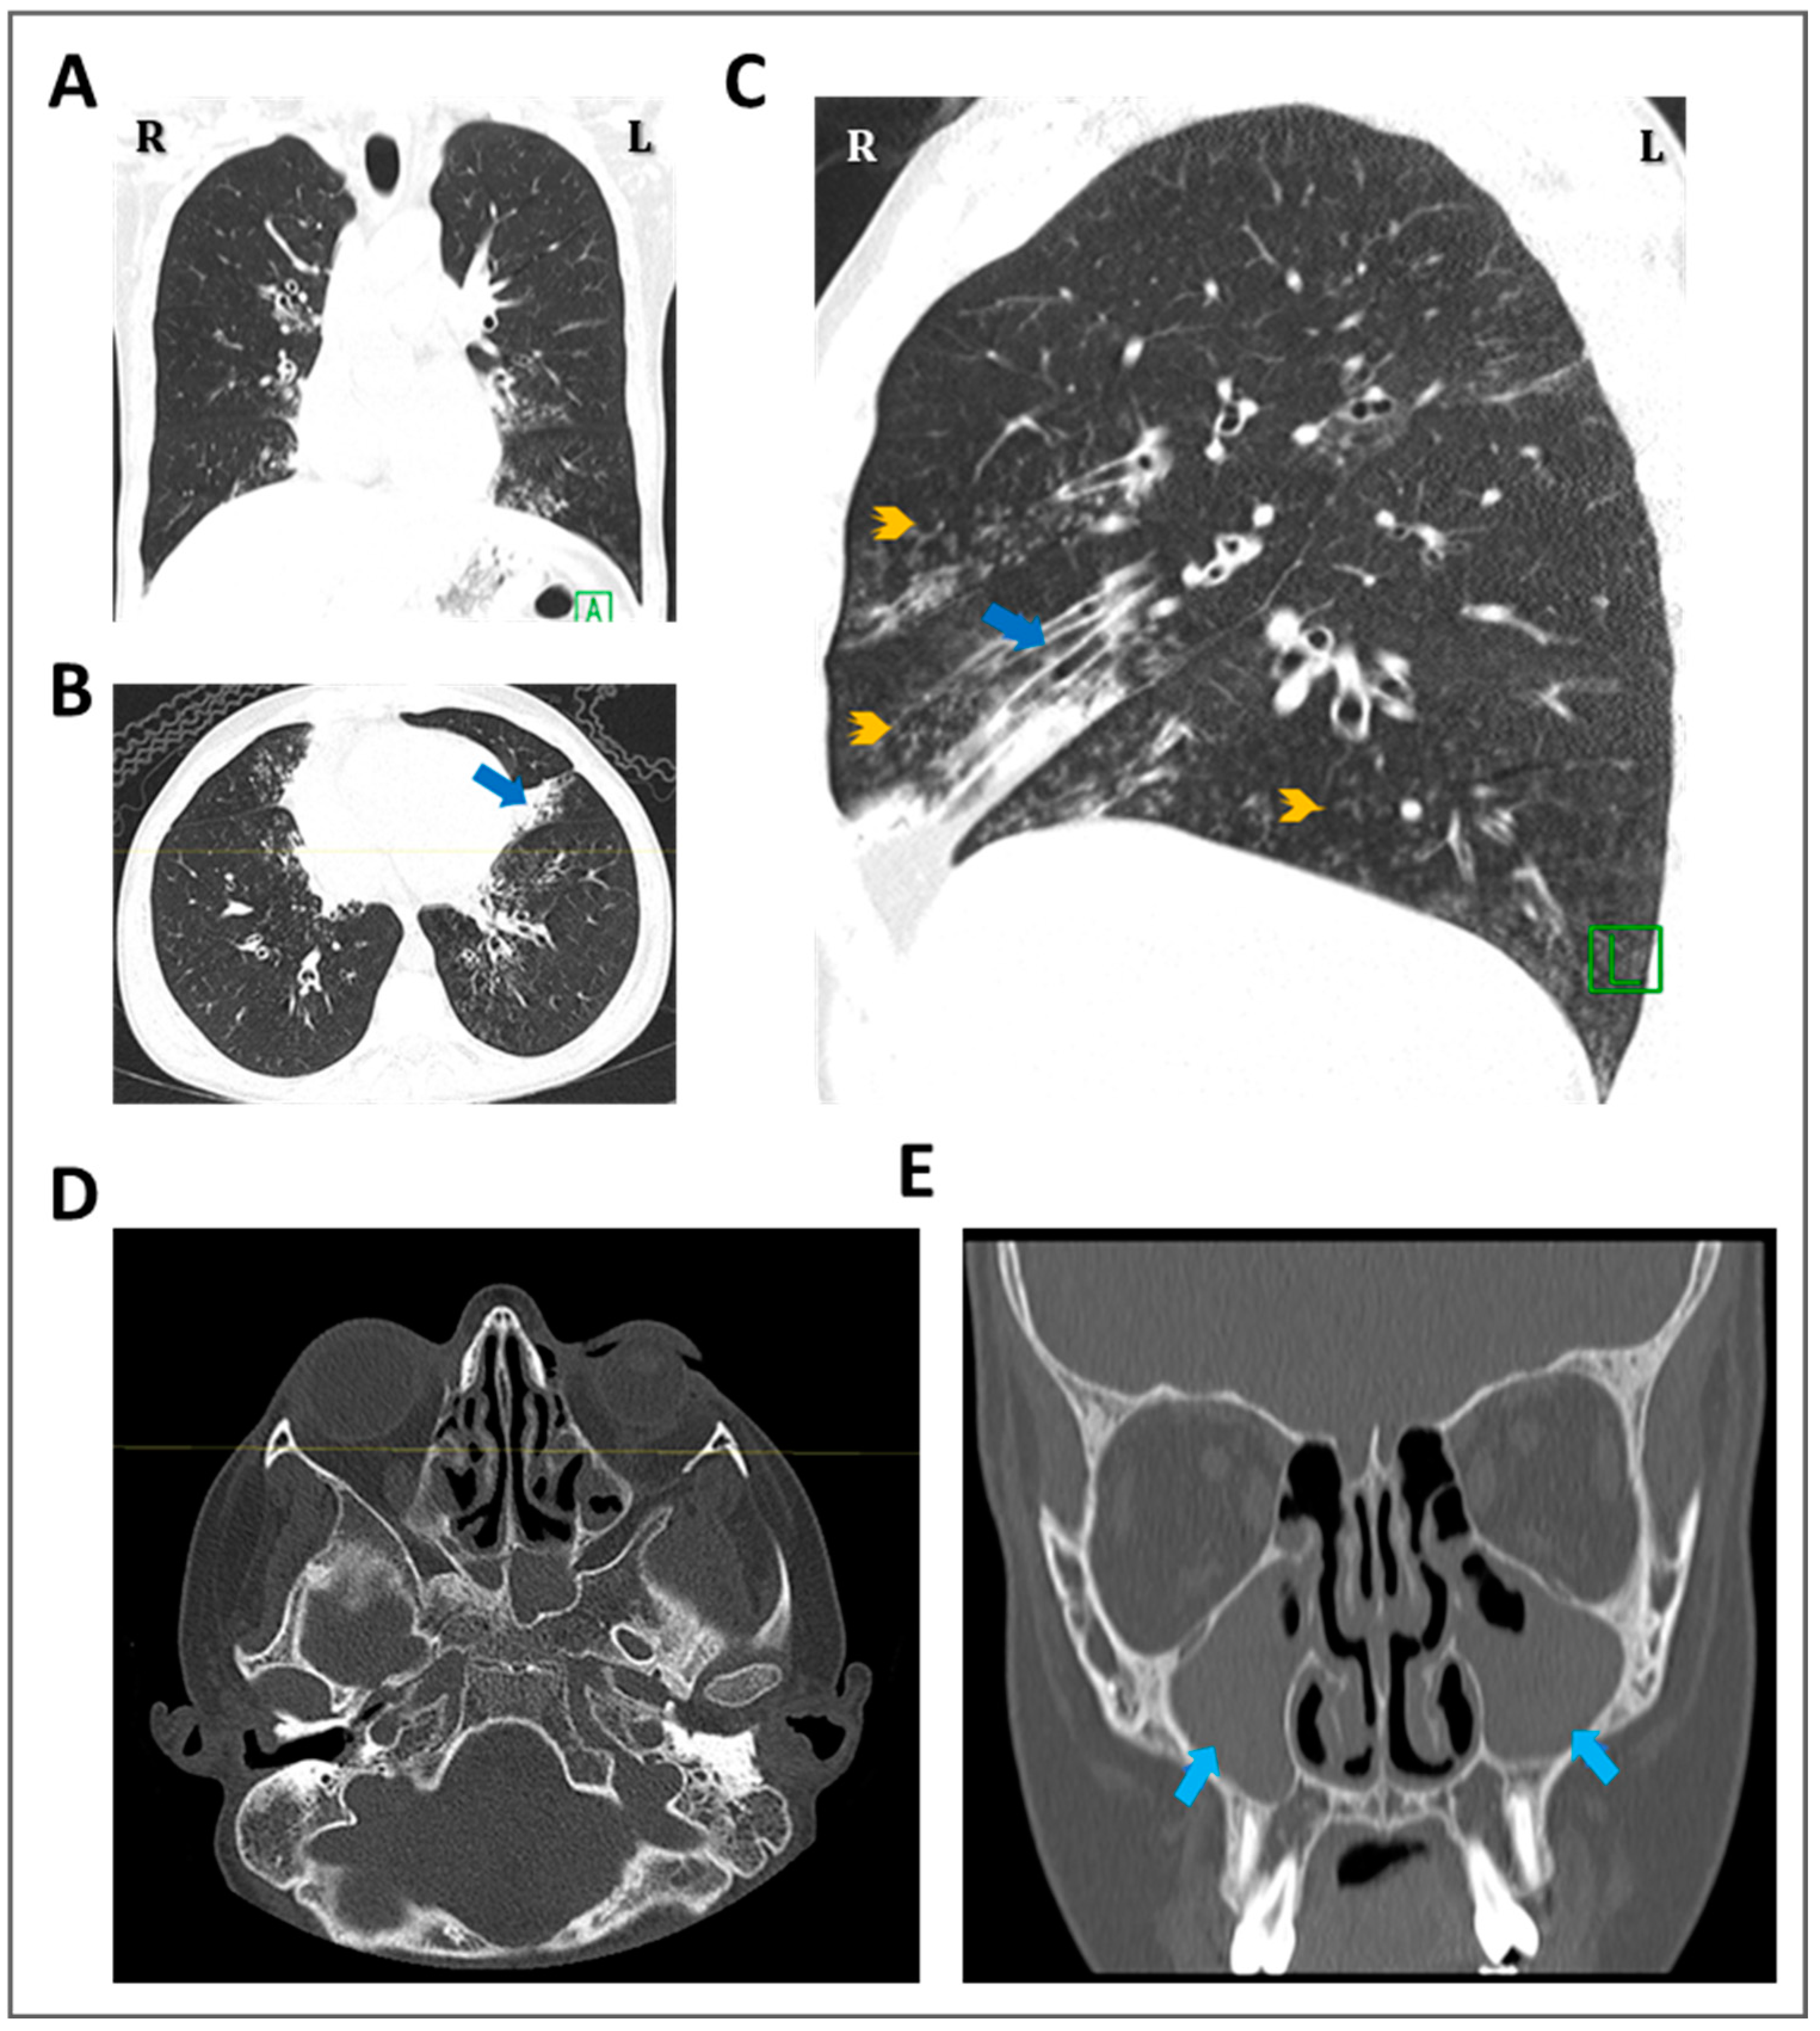

Genetics of Primary Ciliary Dyskinesia

3.3. Detection of Ultrastructural Defects of the Cilia